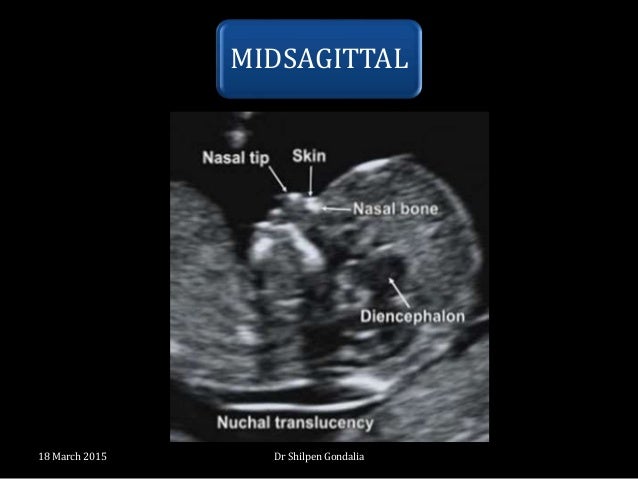

The earlier in pregnancy a scan is performed, the more accurate the age assignment from crown-rump length . The initial age assignment should not be revised on subsequent scans 5 . Overall, the accuracy of sonographic dating in the first trimester is ~5 days (95% confidence range) .

The earlier in pregnancy a scan is performed, the more accurate the age assignment from crown rump length . The initial age assignment should not be revised on subsequent scans 5 . Overall, the accuracy of sonographic dating in the first trimester is ~5 days (95% confidence range) .

Other benefits of the 11-13+6 weeks scan include confirmation that the fetus is alive, accurate dating of the pregnancy, early diagnosis of major fetal abnormalities, and the detection of multiple pregnancies . The early scan also provides reliable identification of chorionicity, which is the main determinant of outcome in multiple pregnancies .

The aim of this document is to provide guidance for healthcare practitioners performing, or planning to perform, routine or indicated first-trimester fetal ultrasound scans . 'First trimester' here refers to a stage of pregnancy starting from the time at which viability can be confirmed (i .e . presence of a gestational sac in the uterine cavity with an embryo demonstrating cardiac activity) up to 13 + 6 weeks of gestation .